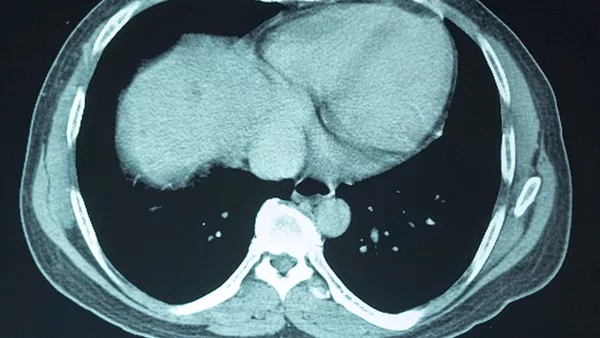

三、羊角風的影像學檢查

過去20年里,神經疾病的影像診斷技術有了突破性的飛速發展。隨著這些先進的非侵入性診斷技術的應用,以前認為主要是功能性異常的羊角風,現發現其羊角 風是由腦結構異常所引起的。原發性"羊角風的比例已大幅度下降了,而有因可循的"繼發性"羊角風越來越多。隨著醫學影像學的廣泛應用,給羊角風的病因診斷 帶來新的飛躍,但應用多年,簡便、經濟、準確的一些檢查手段對某些病人仍不可廢棄。輔助的檢查項目選擇應遵循有的放矢,由簡單到復雜、經濟、準確的原則。